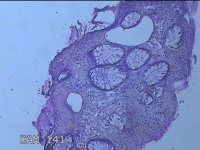

性别

男

年龄

40岁

临床诊断

混合痔

一般病史

反复肛门肿物突出15年。

标本名称

肛门肿物

大体所见

灰白暗红色肿物0.7x0.5x0.2cm一个,表面糜烂。

脱水、透明,浸蜡、脱蜡效果不佳,制片质量差。